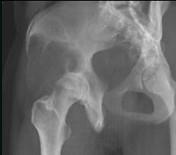

问题 女,31岁,左侧髋部疼痛1月余,有压痛,压之有捏乒乓球感,请结合影像学检查,选出最可能的诊断()

选项 A.骨囊肿 B.骨巨细胞瘤 C.动脉瘤样骨囊肿 D.成软骨细胞瘤 E.骨结核

答案 B